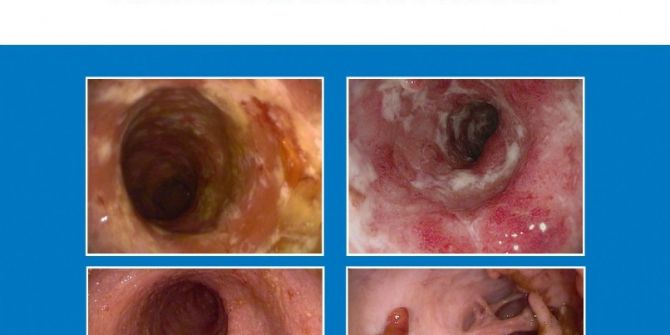

‘İnflamatuar Bağırsak Hastalıkları Atlası’ Kitabı Yayımlandı